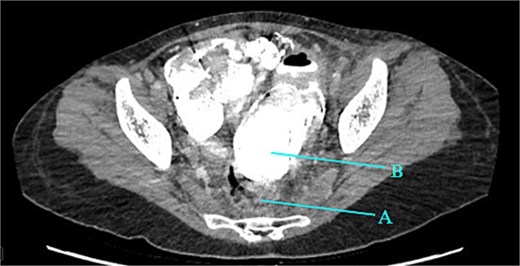

Contrast-enhanced CT of the abdomen and pelvis revealed extensive barium extravasation outlining the peritoneal cavity, accompanied by pneumoperitoneum (Fig. 3). Two barium-outlined, walled-off intra-abdominal collections were identified: one located anterior to the lower pole of the left kidney and the other in the pelvis, anterior to the rectum (Figs 4 and 5). Due to significant barium-related imaging artifacts, the precise site of bowel perforation was not identified. A diagnosis of peritonitis secondary to barium spillage was established, with associated intra-abdominal collections.

Barium-lined intra-abdominal collection (A) anterior to the left kidney (B).

Rectum (A) large barium containing pelvic collection anterior to the rectum, the drain was placed in this collection (B).